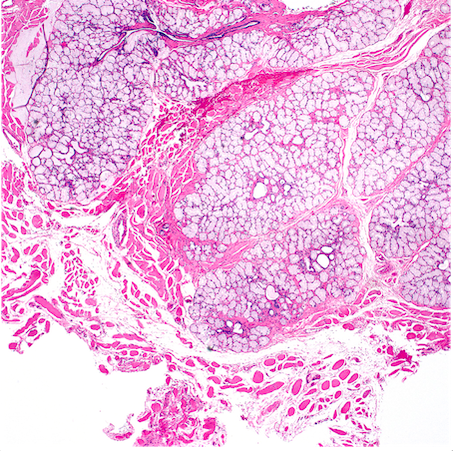

Where in the penis is this histology demonstrative of?

Corpora cavernosa

High power view of interanastamosed slit-like vascular spaces with thin muscular walls.

Complex tridimeensional network of trabeculae.

Vessel walls: thick bundles of smooth muscle. The vascular structures of the corpora cavernosa are thicker adn more complex when compared with those of the corpus spongiosum.

Why is it important to histologically separate corpus spongiosum from cavernosum?

Because tumours affecting cavernosum are a/w a higher rate of nodal metastasis.